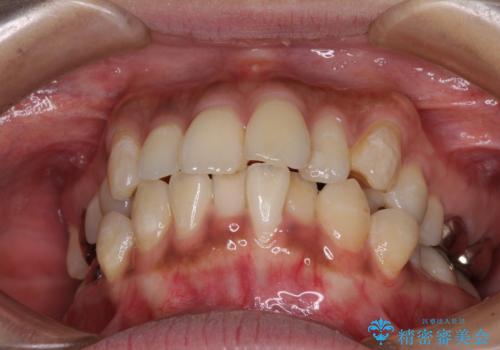

- 口元の閉じにくさを気にして来院された患者様です。

上下ともに歯列が前方に突出していたため、上下左右の第一小臼歯4本を抜去し、ワイヤー装置による矯正治療を行うこととしました。

舌の突出癖による影響もあったため、舌のトレーニングを並行して実施しました。

左下奥歯にむし歯が認められるため、矯正治療後にセラミックインレーにて修復治療を行うこととしました。